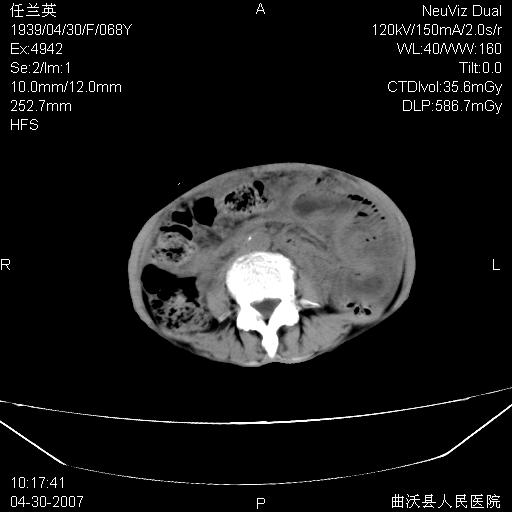

患者,女,68岁,感觉腹部憋涨发硬数天,查b超发现左盆腔有囊性肿物和少量腹水,行ct检查

1.考虑卵巢肿瘤并腹腔广泛性转移可能性大;

2.腹盆腔少量积液。

支持左侧卵巢恶性肿瘤伴网膜、腹膜广泛转移。

难的一见 典型 - 网膜饼  冰冻骨盆 可以当教学片了